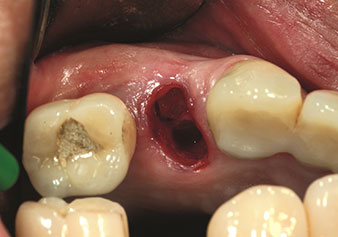

W&H also offers the perfect solution for the internal sinus lift.

Following preparation of the maxillary sinuses with the corresponding instrument set (Fig. 3), the new Z35P instrument (Fig. 4) is used to lift the membrane hydrodynamically. The same instrument set can also be used for piezosurgical preparation of the implant bed in increasing diameters (Figures 3 and 4 included with the kind permission of Dr Mario Kirste, Frankfurt/Oder).

Preparation of maxillary sinus floor and lifting of Schneiderian membrane (Z35P instrument)

Fig. 4: Preparation of maxillary sinus floor and lifting of Schneiderian membrane (Z35P instrument). Photo: © Dr Mario Kirste (Frankfurt / Oder)